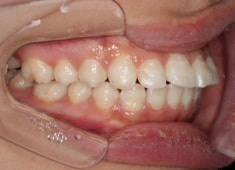

治療前